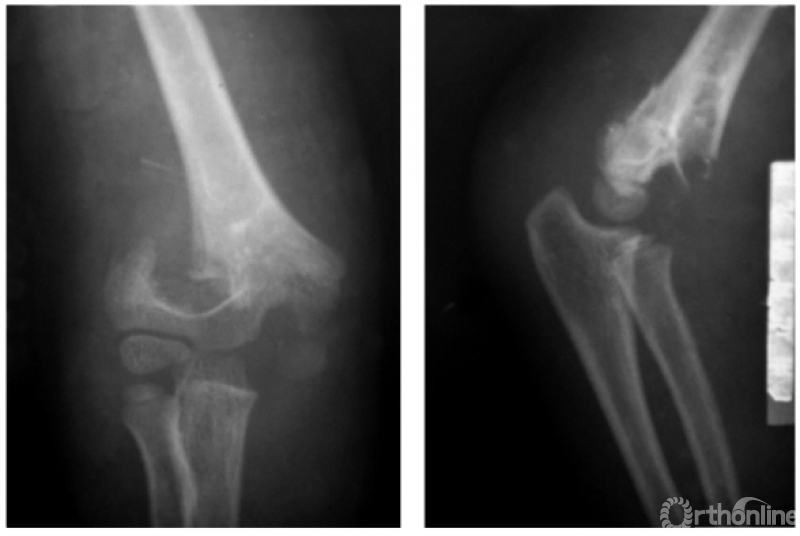

(一) 屈曲型

例:屈曲型兼桡偏,即远折端向前向内移位(图1)。

图1